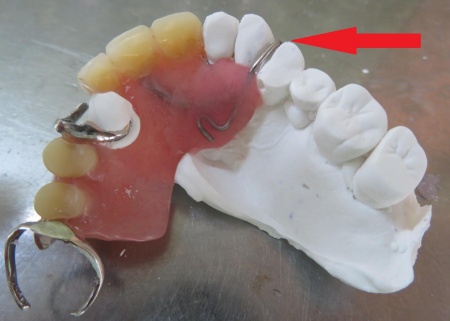

その後、出来上がった型をもとに石こう模型を製作しました。

次に、模型上で人工歯を追加する処置を行います。

折れた部分に合う人工歯を慎重に選び、入れ歯に丁寧に取り付けました。

続いて、左上の前から4番目の歯に合わせて金属ワイヤーを成形し、新しいクラスプを作製します。

歯の形にぴったり沿うよう細かく調整し、入れ歯をしっかり支えられる強さに仕上げました。